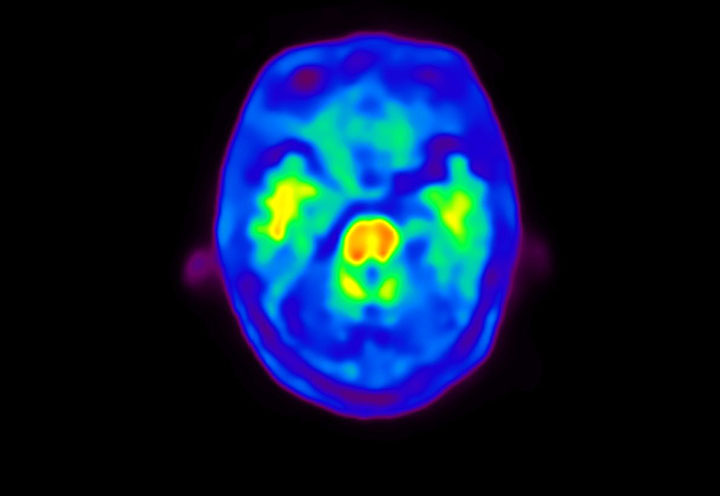

Head / Case4 : Amyloid

Courtesy : Kindai University Hospital

- Imaging protocol

- Injected dose: 3.21 MBq/kg, 18F-Flutemetamol

- Uptake time: 100 minutes

- Scan time: 20 minutes